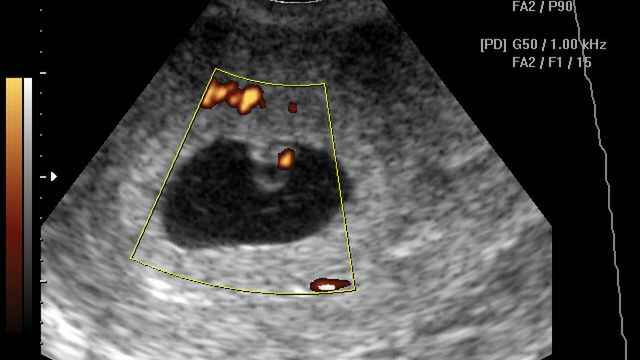

Płód w 6 tygodniu ciąży

Dziecko w 6 tygodniu ciąży ma kompletny układ nerwowy, dynamicznie rozwija się wątroba

Rozpoczyna się rozwój łożyska, które wkrótce przejmie funkcję hormonów